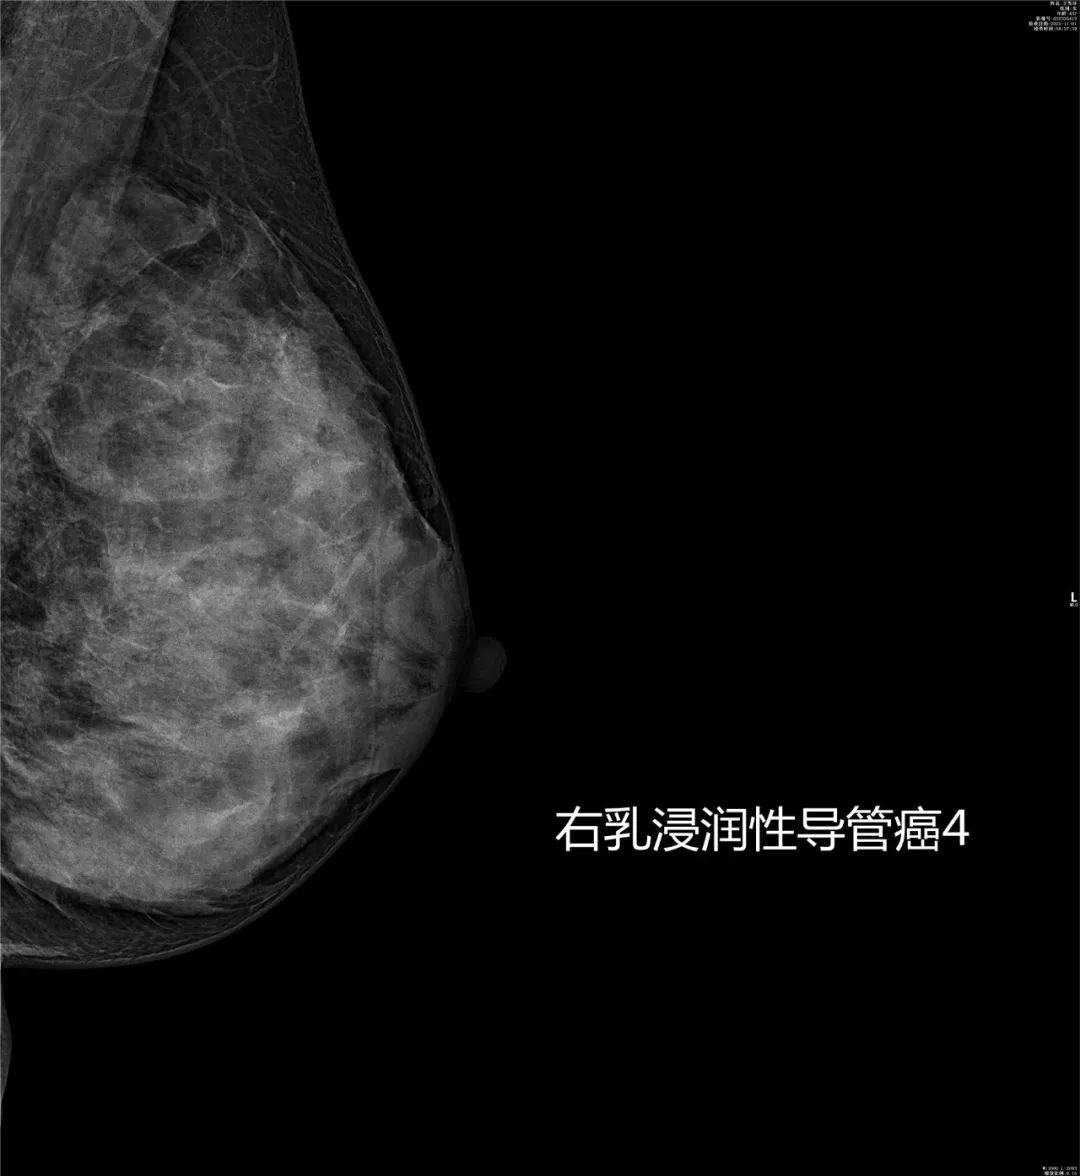

乳腺疾病的诊断与体检筛查